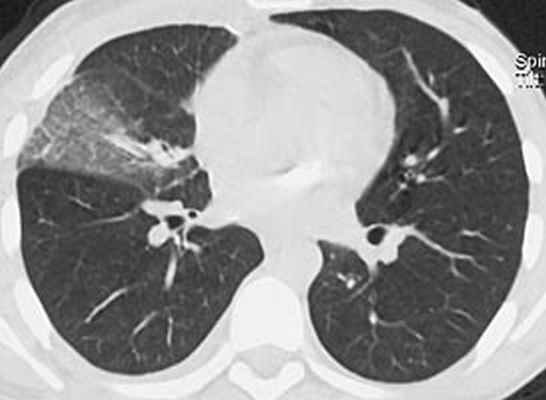

У пациента подтвержден диагноз острого инфекционного эндокардита, недостаточность митрального клапана 3 ст, церебральная эмболия с развитием менингоэнцефалита. Была продолжена терапия ванкомицином и таваником, на фоне которой сохранялась фебрильная лихорадка до 38,5С, в связи с чем проведена смена антибактериальной терапии на линезолид 1,2 г/сут. Однако на фоне терапии сохранялась лихорадка 37,8С. Наличие неконтролируемой инфекции, перенесенная эмболия, наличие крупной вегетации на митральном (наиболее эмбологенном) клапане, явились показанием к протезированию клапана. Осмотрен кардиохирургом. На 7 сутки пребывания в стационаре больному выполнена операция (академиком РАН Шевченко Ю.Л.) санации камер сердца, протезирование митрального клапана протезом Мединдж – 25 в условиях искусственного кровообращения и фармакохолодовой кардиоплегии. Интраоперационно у основания передней створки митрального клапана обнаружен абсцесс диаметром до 1 см. В послеоперационном периоде продолжена терапия ванкомицином 2 г/сут, ципрофлоксацином 0,8 г/сут. На фоне терапии сохранялась лихорадка до 37,9С. В связи с этим пациенту выполнена компьютерная томография органов грудной клетки:

В средней доле правого легкого массивный участок снижения воздушности легочной ткани с очагами инфильтрации, занимающий практически весь объем доли. Диагностирована госпитальная пневмония в средней доле правого легкого. Учитывая сохраняющуюся лихорадку, проведена смена комбинированной антибактериальной терапии на тиенам 2 г/сут в сочетании с линдацином 2г/сут. Лишь после назначения авелокса 0,4 г/сут с римфапицином 0,6 г/сут достигнута стойкая нормализация температуры тела, исчезновение инфильтративных изменений в легких. Нормализовались лабораторные показатели: гем. – 126 г/л, лейк. 8,1х109/л, п - 1%, с – 38%, СОЭ 12 мм/час. Контрольная чрезпищеводная ЭхоКГ без патологии. В течение последующих 1,5 лет рецидива инфекции не было. Температура тела, ЭхоКГ, лабораторные показатели в норме. Клиническое наблюдение представлено острым по началу инфекционным эндокардитом, при котором летальность приближается к 100%. Антибактериальная терапия как и в нашем наблюдении, редко бывает эффективной. Обычно в ранние сроки, особенно при поражении митрального клапана, развиваются множественные эмболии. Хирургическое лечение должно выполнятся как можно раньше, промедление с операцией могло привести к развитию новых более грозных осложнений, которые могли стать непреодолимым препятствием к хирургическому лечению. Современная оперативная техника позволяет не дожидаться санации клапана антибиотиками, а провести хирургическую санацию очага внутрисердечной инфекции в ранние сроки заболевания при наличии показаний к операции.